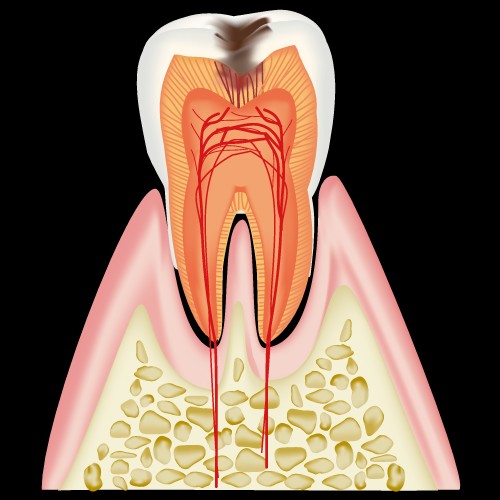

まずは、健康な歯の図です。

歯は三層に別れていて

- エナメル質

- 象牙質

- 歯髄

と呼ばれ、どこまで到達したか、が分類の基準となります。

C0:白濁もしくは着色のある歯

C1:エナメル質が脱灰した初期の虫歯

C2:象牙質まで進行した虫歯

C3:歯髄まで進行した虫歯

C4:歯の根だけが残った状態